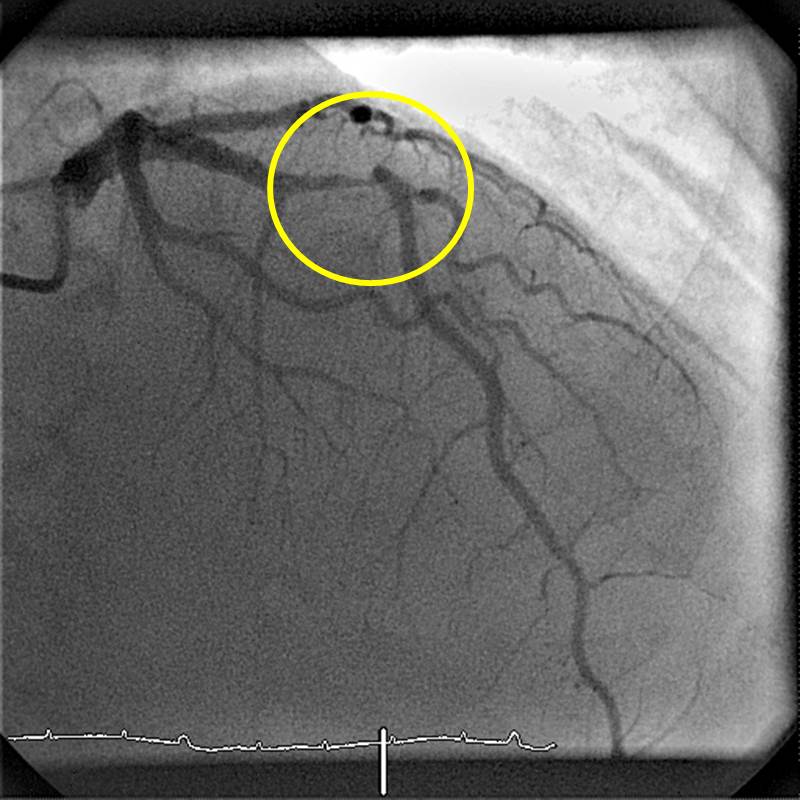

RIVA vor Stent

Hochgradige Stenose der Vorderwandherzkranzarterie (Markierung durch gelben Kreis)

Ein Stent ist ein Geflecht aus Metall, das auf einem Ballonkatheter eng zusammengefaltet ist und über einen dünnen Draht in die Stenose geführt wird. Mit hohem Druck, z. T. mit mehr als 20 bar, wird der Stent mit dem Ballon in die Wand der verengten Herzkranzarterie gedrückt.

RIVA Stentimplantation

Aufdehnung der Stenose durch Implantation eines Stents, der mit einem Ballon in der Stenose entfaltet wird. Der Ballon ist in dem Bild dunkel gefärbt.

Der Ballonkatheter wird nach Entleeren wieder herausgezogen und der Stent bleibt unverändert in der Arterienwand, sodass der Blutfluss im Bereich der Stenose wieder normalisiert ist.

RIVA nach Stent

Darstellung der Vorderwandherzkranzarterie nach Stentimplantation. Die Stenose ist nicht mehr nachweisbar (Markierung durch gelben Kreis).